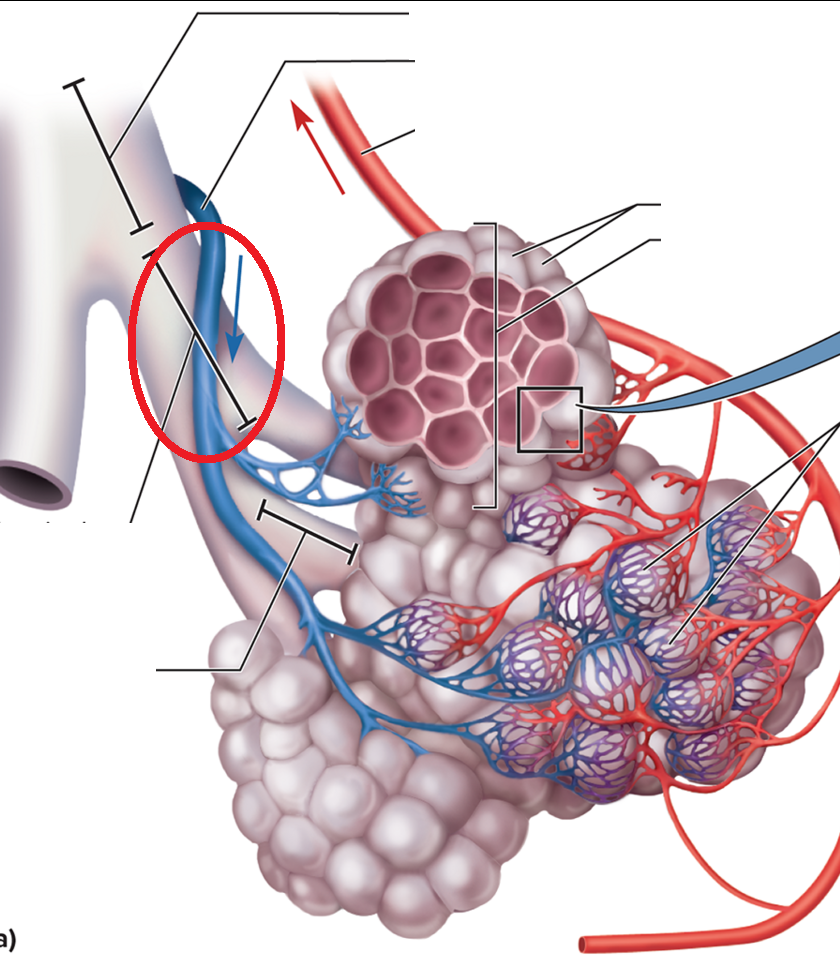

resp bronchiole

Alveolar duct BT

Alveolar sac BT

Alveolus BT